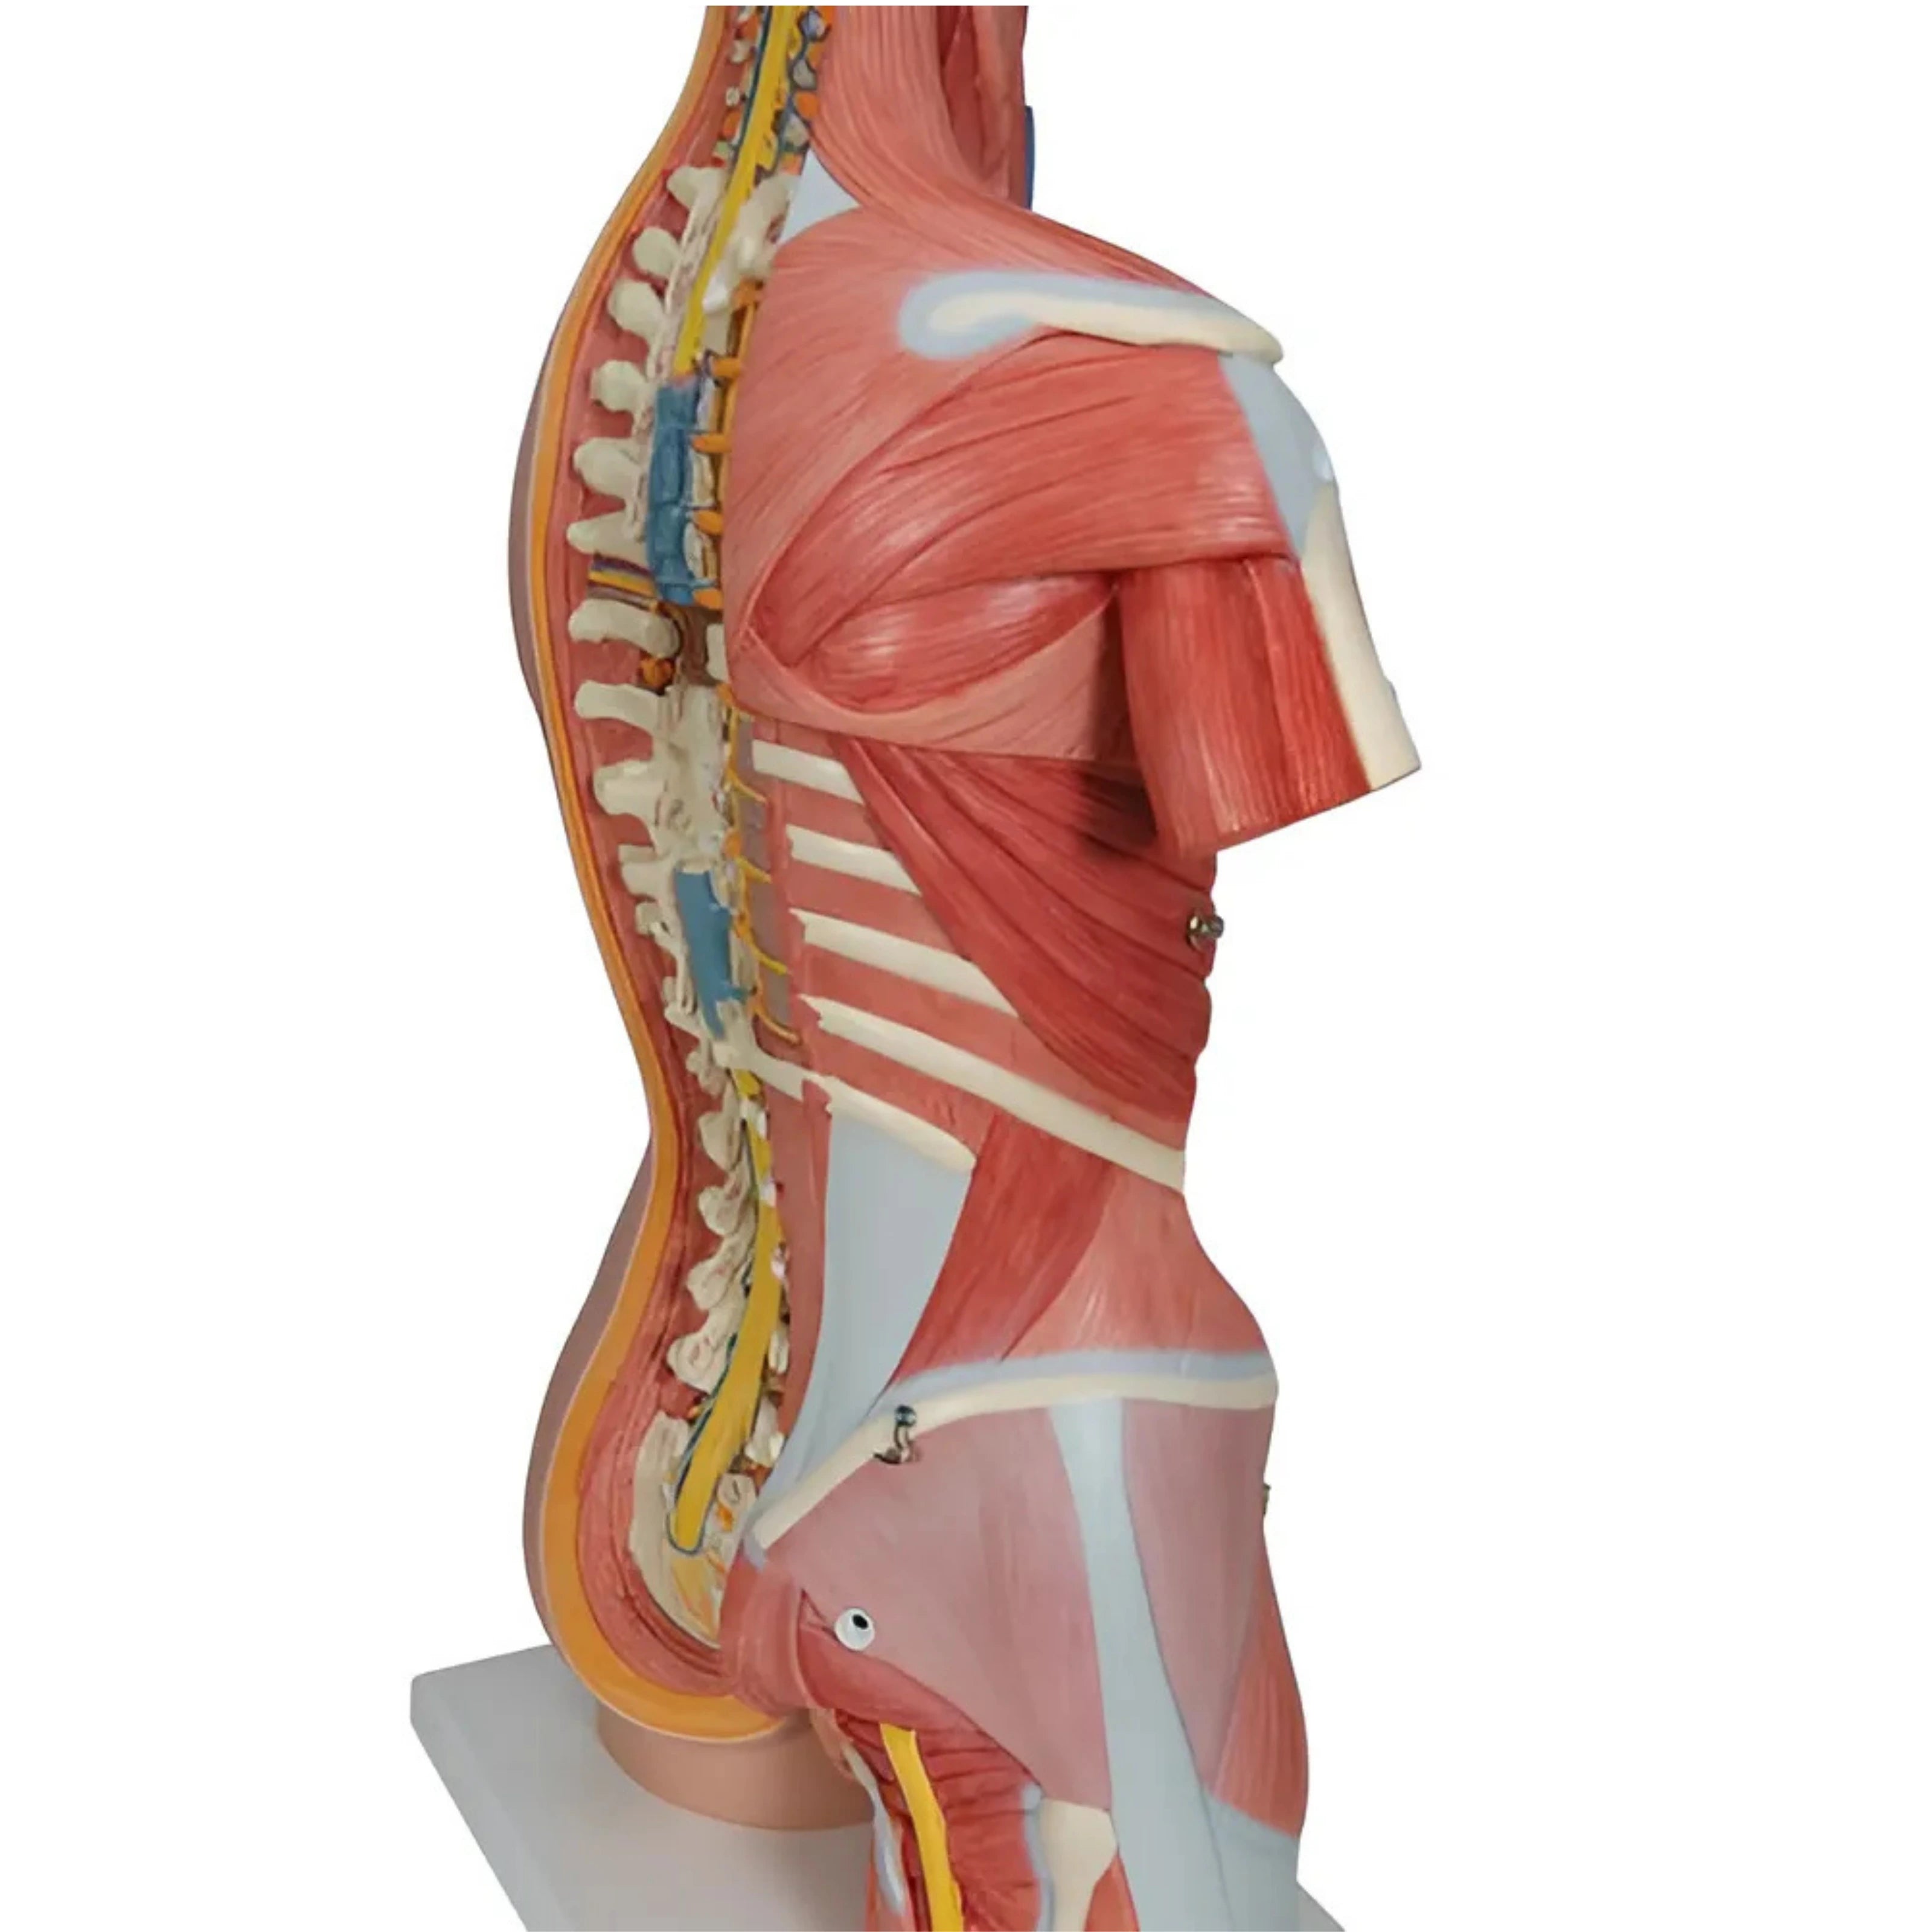

Torso clásico con espalda abierta, 18 partes - 3B Smart Anatomy

Precio de venta$33,762.96